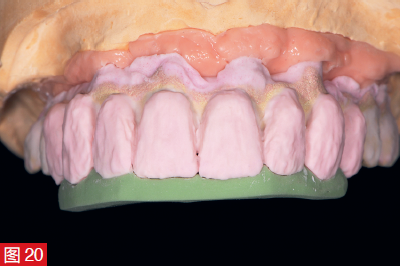

1993 年的聲明 - “在高笑線的情況下,上頜骨的彈性牙齦植入物可以改善美學和言語” - 原則上是正確的。然而,由于未經證實、耐用性差和衛生問題,不再推薦使用牙齦修復體。不僅如此,人們還試圖用粉紅色的瓷粉來完成這部分,以盡可能地模仿自然條件。通過牙冠和牙齦釉質顏色的完美協調,現在可以很好地模仿或再現紅白美學。對于高質量的修復體,最終修復體選擇了分層瓷貼面,而不是人工牙排的形式(圖 20 和 21)。在這種情況下,中間橋體區域設計為橢圓形組織表面形成,然后用復合樹脂嵌體封閉入口(圖 24 和 2<@)。5). 最后,調整動靜咬合。然后用復合樹脂嵌體封閉入口(圖 24 和 2<@)。5). 最后,調整動靜咬合。

圖 20:基架的逐步手動精加工。操作時可使用硅橡膠模板(綠色)作為輔助。